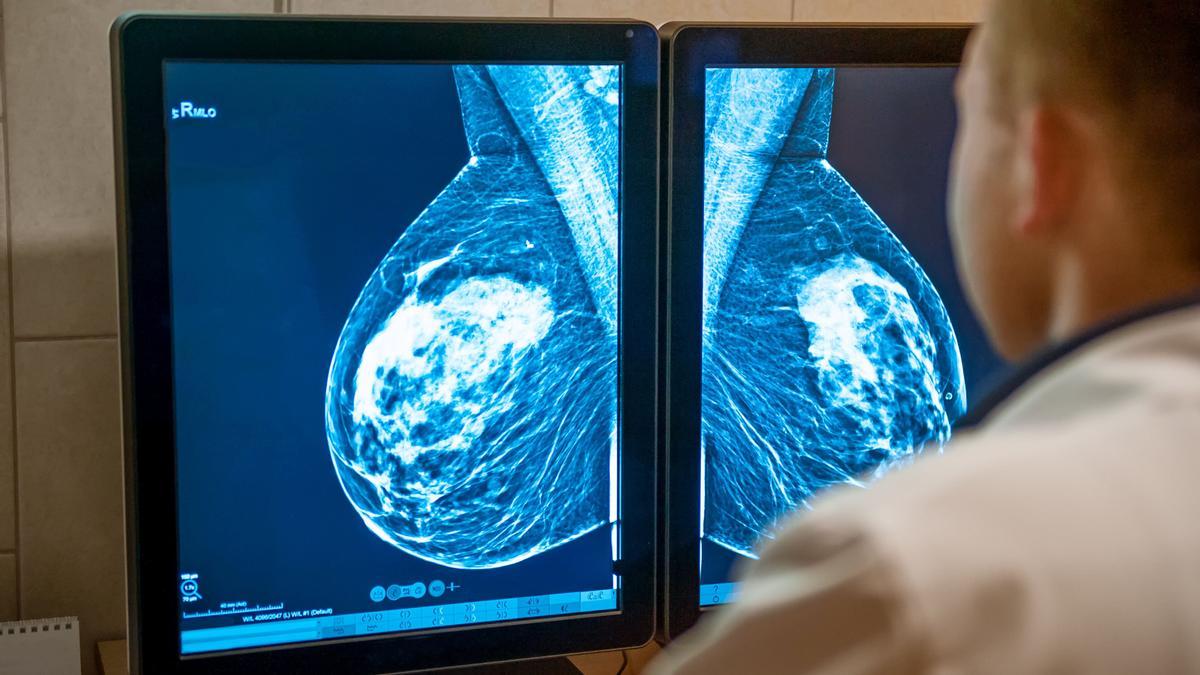

Un doctor analiza una mamografía. / FdV

Ni rosa ni bonito. En España se diagnostican cerca de 37.000 nuevos casos de cáncer de mama cada año, y aunque la mayoría se detectan en fases tempranas, alrededor del 5 al 10% de las pacientes debutan con metástasis, es decir, cuando el tumor ya se ha extendido a otros órganos del cuerpo. María Rouco Costas, es una de ellas. «El cáncer es vomitar en un cuarto de baño sin poder moverte» relata para FARO